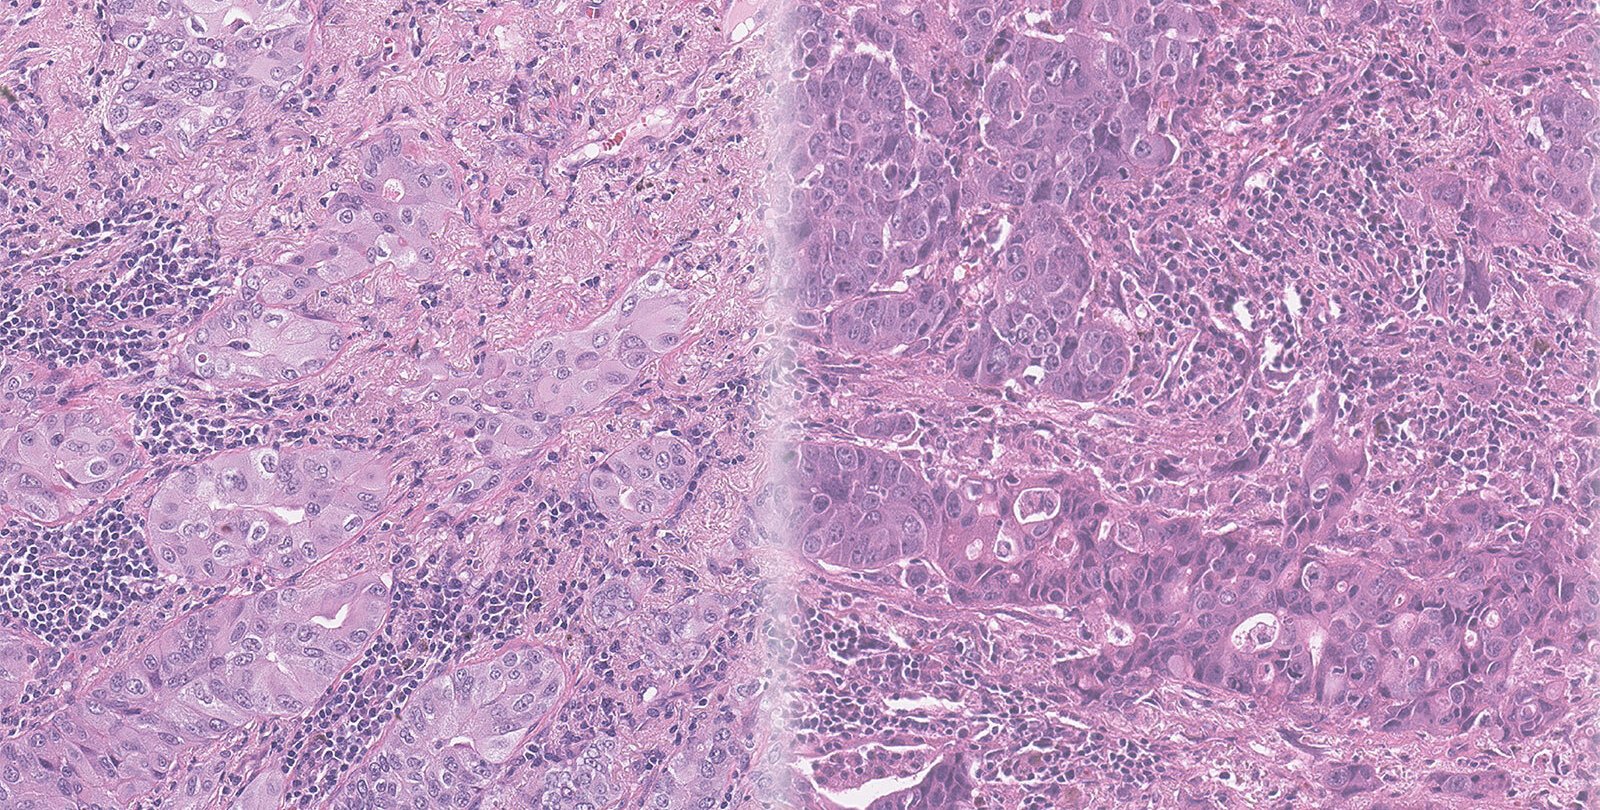

The team worked with data and biopsy images collected from 118 NSCLC patients at Washington University School of Medicine in St. Louis. Typically, a pathologist reviews such images, scouring them for abnormalities within the cells that might suggest the cancer is progressing.

Caltech electrical engineers led by Yang used hundreds of thousands of image tiles pulled from those 118 original biopsy images to train a type of AI program called a deep-learning network. They also provided follow-up data about which patients went on to develop brain metastases within five years of diagnosis and which did not.

"We essentially asked the network to learn from all these images, to pick out some features from the contextual information that could indicate something about a patient's outcome," says graduate student Haowen Zhou, first author of the new paper. Then the network was given 40 additional biopsy images and asked to determine whether the patients had gone on to experience brain metastases.

The AI network was able to correctly predict whether an individual NSCLC patient had experienced brain metastasis 87 percent of the time. In contrast, four expert pathologists who reviewed the same biopsy images were able to make the correct predictions only 57 percent of the time.

"Our study is an indication that AI methods may be able to make meaningful predictions that are specific and sensitive enough to impact patient management," says Richard Cote, head of the Department of Pathology & Immunology at Washington University School of Medicine and co-principal investigator of the new study. He notes that for the earliest-stage NSCLC patients (those classified as stage I), the AI results were even better than those for the whole study and that these predictions were based solely on basic, routinely processed microscopic slides. By giving the AI information on additional factors such as the severity of the disease and any additional biomarkers, the researchers expect that they will be able to improve the predictive powers of the AI program going forward.